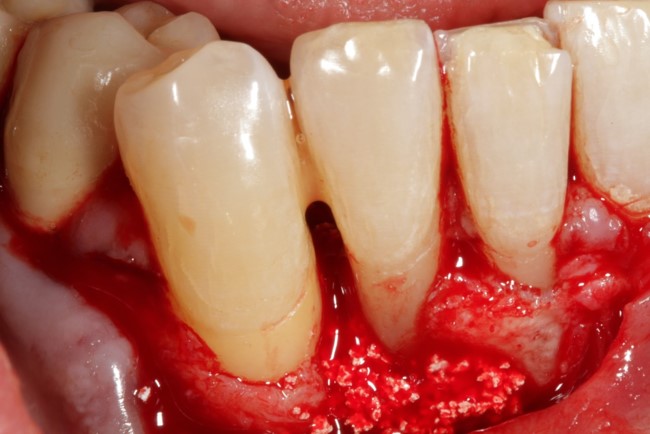

04/08 - Intra-operative view of the defect area.

Non-contained intrabony defect treated using Straumann® Emdogain® and a synthetic bone grafting material - Prof. Dr. Dr. A. Kasaj